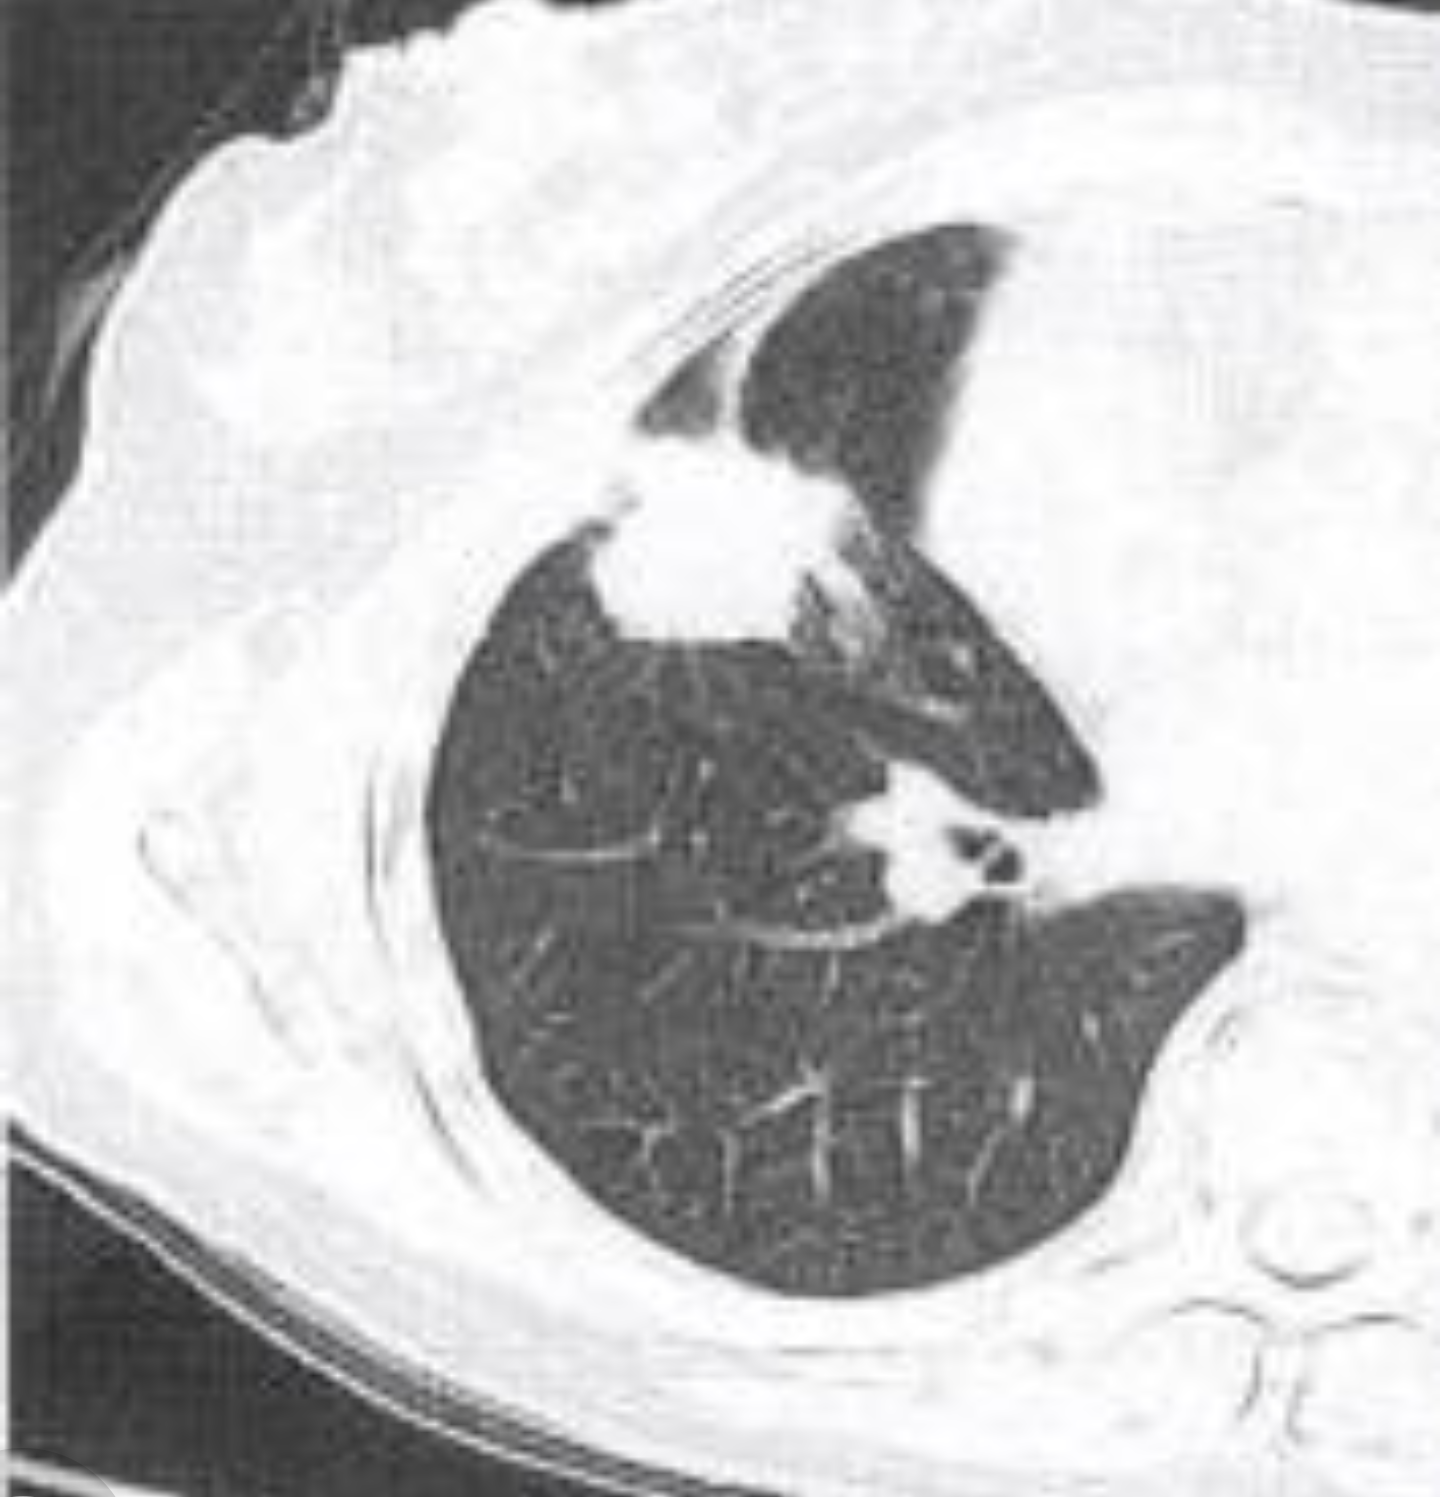

左下肺背段见分叶状结节影,会是什么?

肺部结节边缘凹凸不平的分叶状轮廓,是该征的主要x线表现,对于较大的